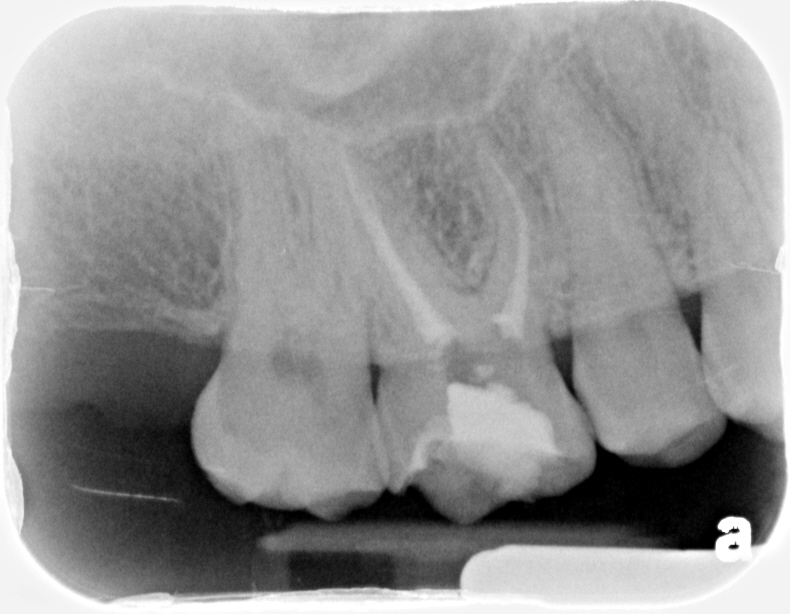

Tooth vital- tooth necrotic

# teeth with MB2 present- able to cleanse and shape the MB2 – MB2 join

MB1 – teeth I consider calcified that no MB2 was found – total # of 1st

molars treated

MB2 distance from MB1 – join MB1

1-0

1-1-1-0-1

1mm-yes

So this MB2 joined the MB1 very early within first few mms. Completed in Mendota